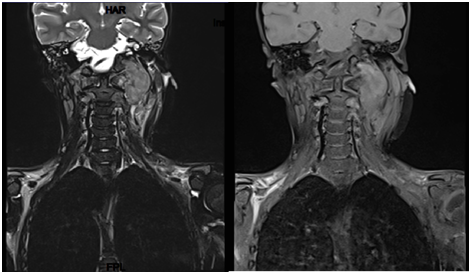

7 years old boy presented with history of left neck mass, headache and weight loss for 1-month duration, with limited range of motion of the neck and increasing pain in that region for 5 days before he was referred to our hospital. Physical examination revealed left upper cervical swelling measuring 5x6 cm in diameter, firm in consistency and attached to the underlying structures, no neurological deficit of signs of respiratory compromise was observed. His initial laboratory results are shown in Table 1. Cervical lymph node biopsy revealed reactive lymph nodes, negative for granulomata and negative for malignancy. Magnetic resonance imaging (MRI) of the neck (Figure 1) showed evidence of perivertebral/retropharynegal large multilobulated soft tissue mass measuring about 7.9x8.7x6.9 cm in transverse, craniocaudal and at the posterior dimensions respectively, extending in the nasopharyngeal region, and extending opposite to the skull base, clivus and upper cervical vertebra body posteriorly with the extension through the neural foramina of C1 and C2 vertebrae and causing bony erosions, extending into the spinal canal, however the signal intensity of the spinal cord was preserved, with narrowing of the right vertebral artery and questionable tumour involvement at the level of C1. Superior extension of the mass is seen obstructing the nasopharynx, anteriorly the mass is seen compressing the nasopharynx and exerting mass effect on the oropharynx with no patent airway seen around endotracheal tube. Infiltration of the hard palate and palatine tonsils were seen, laterally the mass seen compressing the carotid vessels bilaterally with suspicion of marked compression and occlusion of the left jugular vein, however the carotid arteries were patent. The patient underwent incisional biopsy of the retropharyngeal mass and bilateral bone marrow aspiration & biopsy. During surgery patient was electively intubated and due to difficulty in extubating and critical obstructed airway a tracheostomy tube was inserted to ensure patent airway. Histopathological examination of the retropharyngeal mass showed small blue cells with scant cytoplasm (Figure 2). Immunohistochemical studies showed that tumor is positive for CD99 and Vimentin, negative for Myogenin, TTF-1, Pankeratin, Desmin, Chromogranin,CD45, Synaptophysin, SMA, MSA ,CK7,EMA,CD56, CD34, and PAX5. Fluorescence in situ hybridization (FISH) study showed fusion of the ESWR1/FLI1 genes associated with the translocation t(11;22)(q24.3;q12.2) Thus radiological, histological and immunohistochemical finding were confirmatory of Ewing sarcoma of the retropharyngeal space. Bone scintigraphy showed no evidence of bone metastasis. As incidental finding on CT abdomen revealed a single hypertrophied right kidney with mild hydronephrosis. Renogram was done and showed partial obstruction, Later patient developed acute renal injury and anuria, ultrasound kidney showed severe hydronephrosis with obstruction. His case was discussed with the infectious disease and nephrology physicians and the decision was made to insert double J stent under interventional radiology, signs of renal function recovery were seen in the next 2 days. Patient started on European Ewing tumour Working Initiative of National Group 99 (EURO-E.W.I.N.G99) protocol, ended first cycle of chemotherapy that contained vincristine, ifosfamide, doxorubicin and etoposide and supported with G.C.S.F (VIDE), with acceptable tolerability. Planned for evaluation after 2 cycles for the local control option.

Figure 2 MRI of the soft tissue of the neck showing a large destructive soft tissue mass measuring about 7.9x8.7x6.9cm in diameter (coronal and axial view).